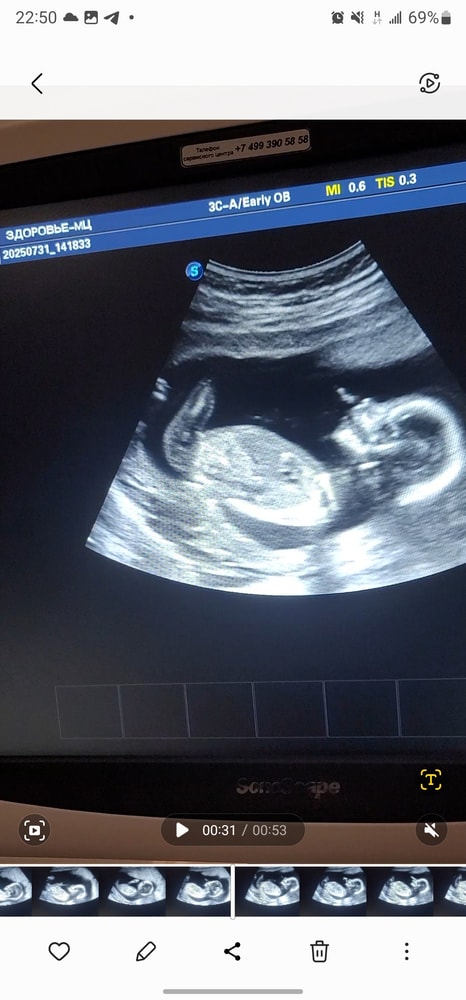

Ждём доченьку 😊🥰 УЗИ 15 недель

Пол малышаВ четверг ходила на узи, где врач дал 80% гарантии на девочку. В предыдущем посте кидала фото с узи)